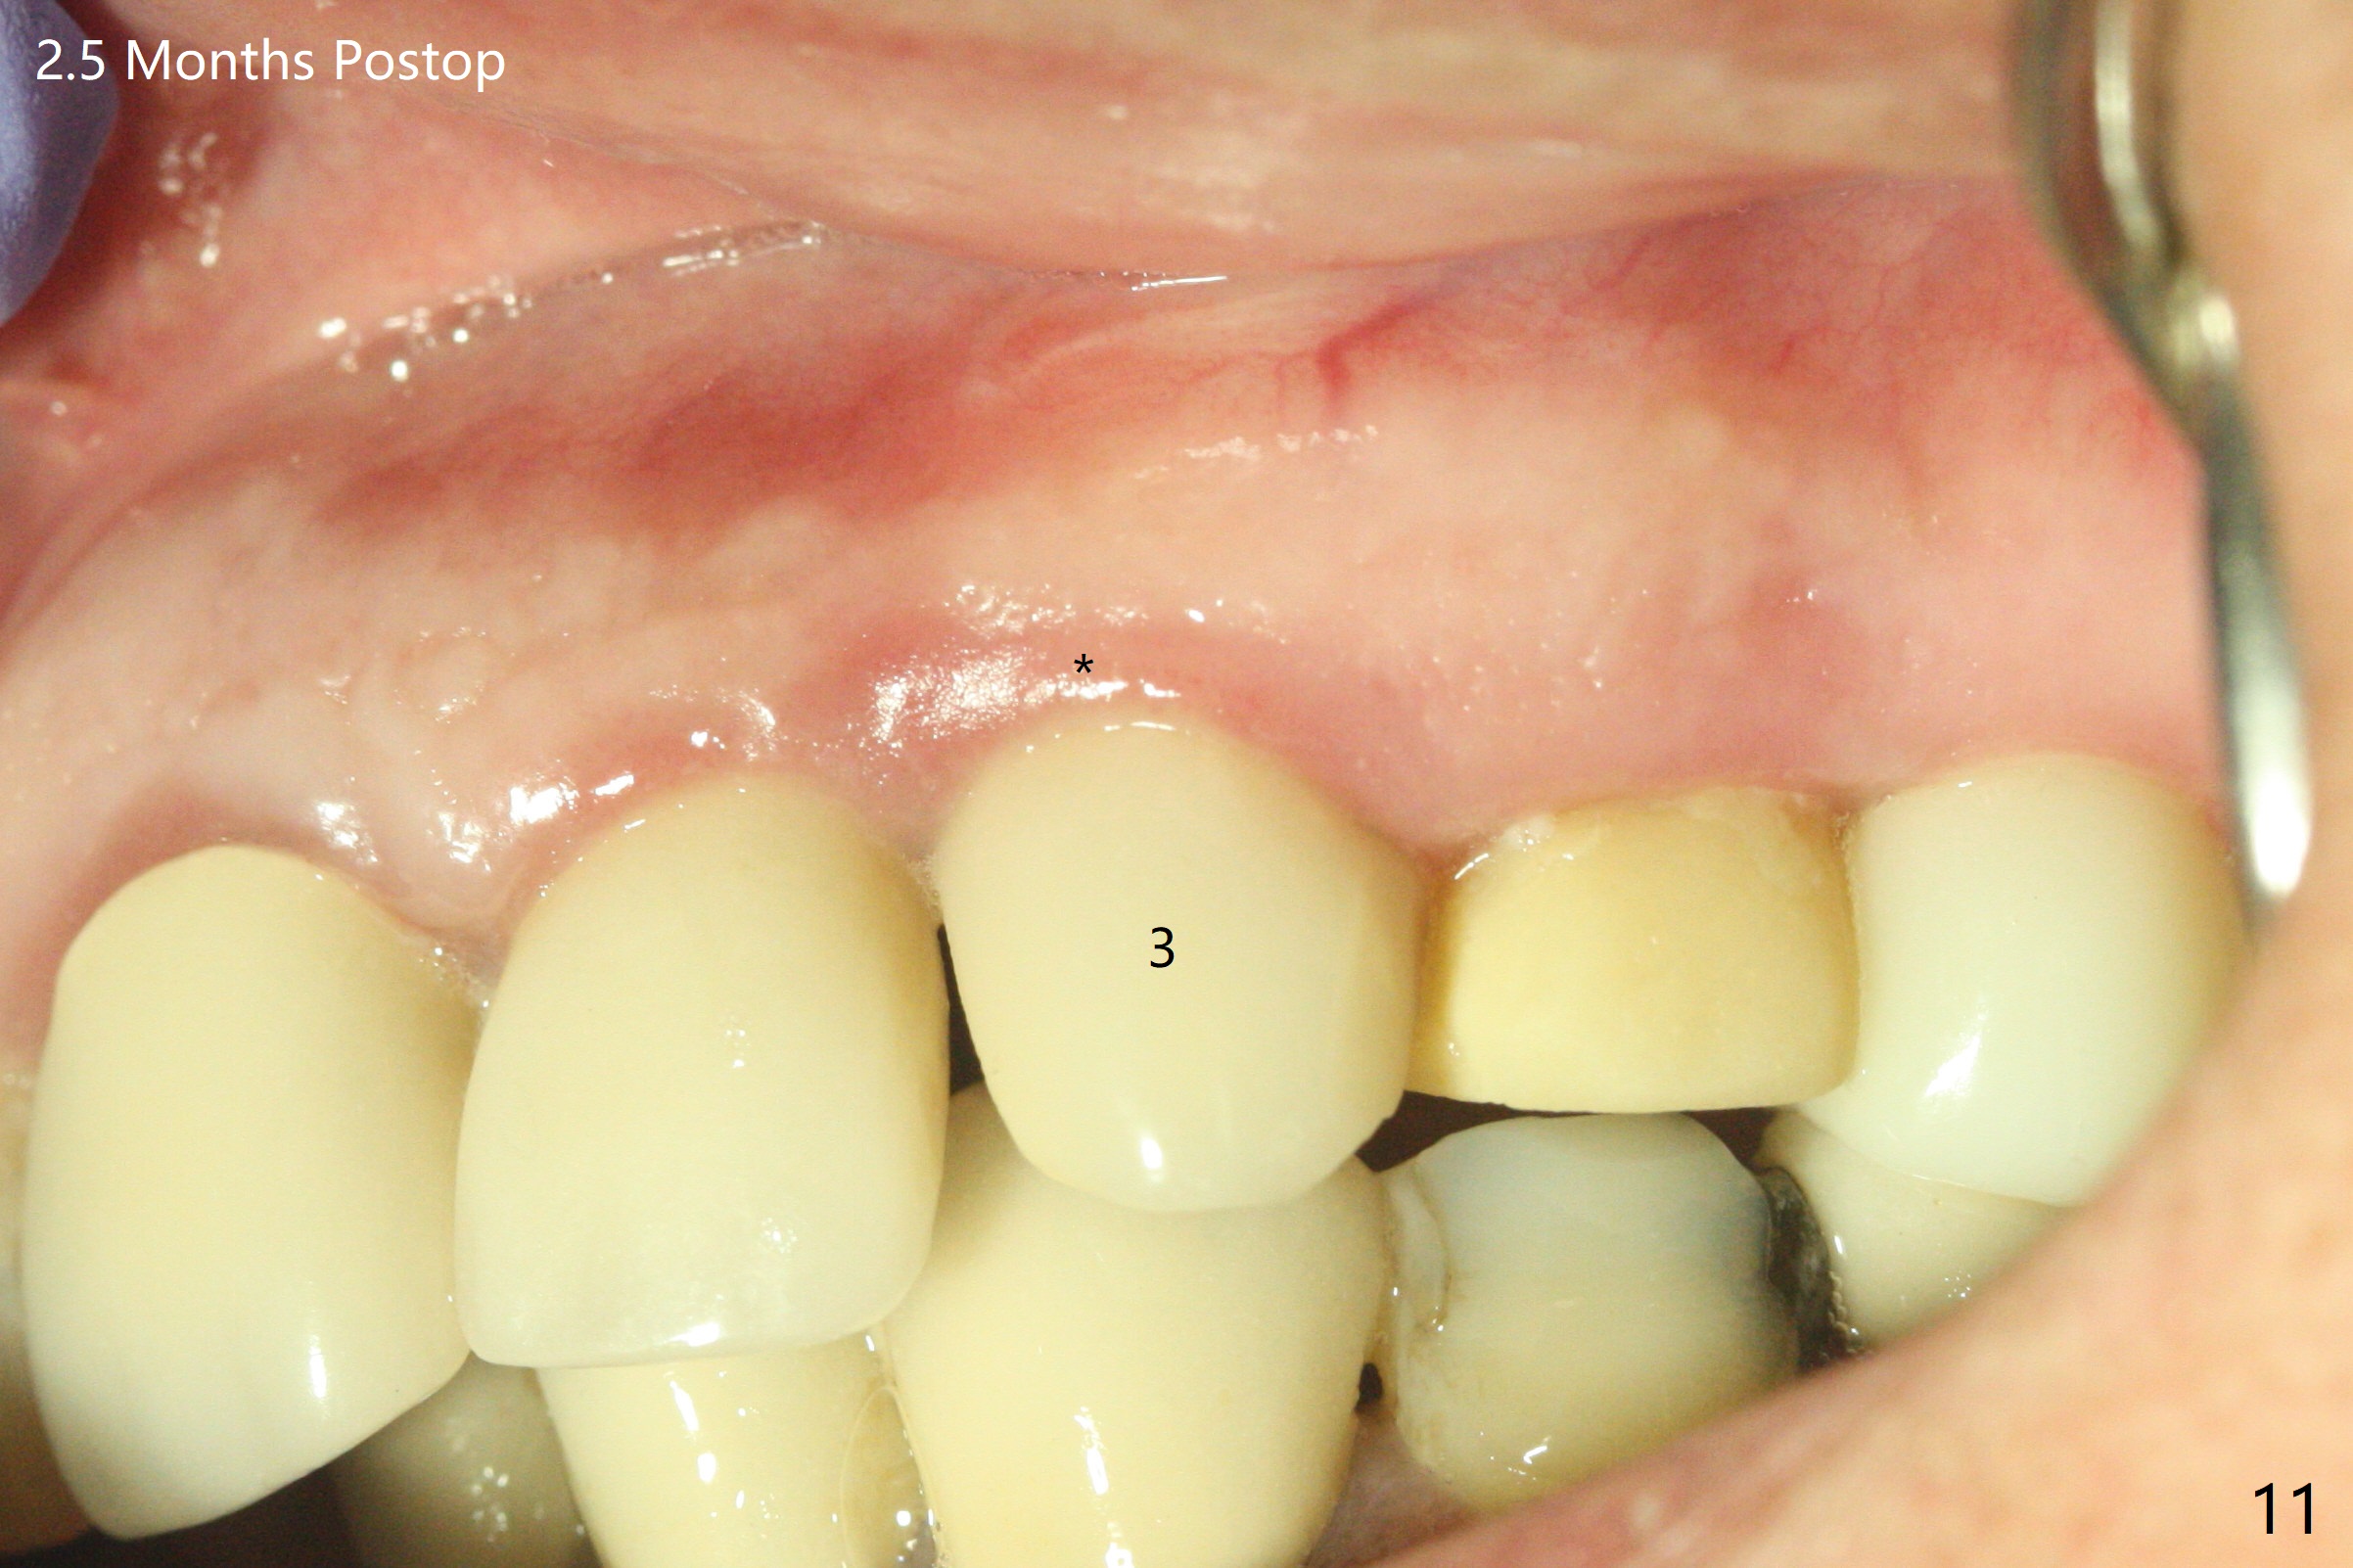

52岁女左上4颊侧牙龈显著肿胀(图一:*(颊侧骨板缺失))伴有瘘道(<),拔除前,在3植牙牙冠切缘舌侧形成开口(图二:*,准备纠正基台不全就位(<);4初步钻洞不正。改变钻头方向后(图三),完成植体放置(图四),并且安置修复基台(4.5x4(2))。磨去3牙冠近中面(图六:*),牙冠和基台反时针旋转(图六:弯箭头),基台完全就位(图四:箭头),调𬌗后,制作4临时牙冠(图六),放置后者前,覆盖半张PRF膜(促进下面粘性骨粉愈合)。图五,六颊侧隆起是因为下面放置许多粘性骨粉。图七是术前CT3D图像(冠状切面),显示颊侧(B),腭侧(P)牙根。拔牙后显示中隔(图八:S),植体植入腭侧窝(图九:绿色),四面骨质包绕,包括中隔;为了修复颊侧骨板,首先放置半张PRF膜(红色)紧贴颊侧骨板腭侧/牙龈,防止骨粉从瘘道流失,然后放置粘性骨粉(图十:粉红色)。术后2.5月3颊侧牙龈仍然红肿(图十一,十二:*),可能与基台袖太短有关(2毫米,图二至四),所以更换袖3毫米的基台(图十三)。术后四个月(牙冠粘固)3颊侧牙龈炎症明显减退(资料没有显示)。术后2.5月4颊侧骨板没有塌陷(图十二,与术后即刻对比(图六))。3基台放置太颊侧,所以在牙冠腭侧制作小的开口(图十四:>),让多余粘固剂流出。取模前3螺丝就拧紧(35Ncm),而4由于有大的开口,粘固后才拧紧(30Ncm)。两个邻牙其中一个可以取出,容易去除另外一个牙冠残余粘固剂。